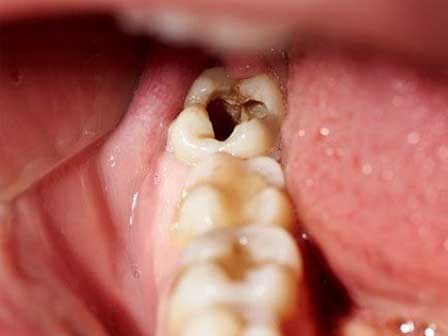

Cách chữa sâu răng tại nhà mẹ nào cũng nên biết

Sâu răng là một căn bệnh phổ biến nhưng bạn không nên coi thường. Hãy cùng chúng mình xem cách phòng ngừa bệnh rất đơn giản tại nhà nhé.